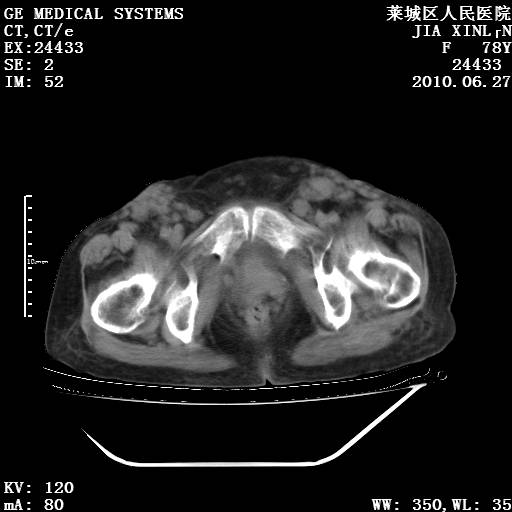

以下是引用胡宇在2010-7-2 19:11:00的发言:[br]神经纤维瘤的特点为:肿块呈多发性、数目不定,少的几个,多的可成百上千难以计数。小的如米粒,大的似拳头,甚至可达十数公斤以上。可松弛地悬挂于皮表,皱褶及松弛可致畸形明显。神经纤维瘤沿神经干的走向生长时呈念珠状,或蚯蚓块状形结节。此外神经纤维瘤皮肤可出现咖啡斑,大小不一,形如雀斑小点状,或大片状,分布与神经纤维瘤肿块的分布无关。肿瘤数目不多的患者,皮肤色素咖啡斑状沉着是纤维神经瘤的重要诊断之一。 本病多发于躯干,有时出现于四肢及面部,患者常合并许多疾病应予重视加以区别。 [br] [br] [br] [br]lyb999说 [br]